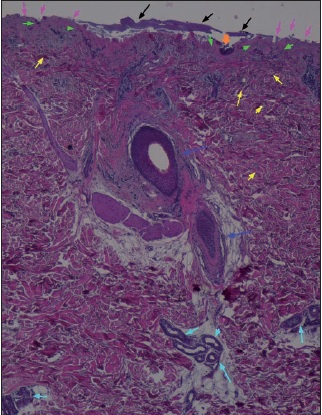

Estudio histopatológico en 3 pacientes: desbridamiento completo de la quemadura en 1 y parcial en 2, con abundante infiltrado inflamatorio linfocítico perivascular postratamiento. Los hallazgos histopatológicos se correlacionaron con la eficacia del desbridamiento valorado clínicamente en 1 de los 3 casos, y con el diagnóstico clínico de la quemadura en los 3 casos.

La realización de biopsias pre y postratamiento en 3 de los pacientes permitió observar 2 casos de desbridamiento parcial de la zona necrótica, siendo 1 caso una quemadura de tercer grado en dorso de mano que precisó de injerto (Fig. 25 a 34, caso 9), y el otro una quemadura previamente tratada con Flammazine Cerio® (Fig. 35 a 45, caso 12). En el tercero de los pacientes biopsiados apreciamos desbridamiento histológico completo de la zona necrótica con preservación de la dermis sana (Fig. 46 a 50, caso 11). Como hallazgos significativos, en las 3 muestras postratamiento evidenciamos un infiltrado inflamatorio linfocítico perivascular (Fig. 36, 40 y 48).

Otro hallazgo significativo de nuestro estudio es el incremento del infiltrado inflamatorio tras el tratamiento (Fig. 36, 40 y 48). Sin embargo, no podemos afirmar que sea consecuencia del tratamiento enzimático ya que no realizamos comparación con zonas de quemadura no sometidas a tratamiento con Nexobrid®. Además, en la literatura existe referencia al infiltrado neutrofílico típico que existe en la zona intermedia de la quemadura (región histológica comprendida entre la zona sana y la zona necrótica de la quemadura), pero el evidenciado en nuestro estudio es un infiltrado linfocítico perivascular que, hasta donde nosotros sabemos, no aparece mencionado en ningún estudio publicado sobre el desbridante Nexobrid®.(21) Aunque desconocemos si este infiltrado es originado o potenciado por el tratamiento con Nexobrid® o bien debido exclusivamente a la progresión de la quemadura, sería necesario estudiar si el posible incremento del infiltrado inflamatorio guarda correlación con la velocidad de curación o con el pronóstico a largo plazo, o bien es únicamente el resultado de la evolución fisiopatológica de la quemadura y no existen diferencias con el infiltrado evidenciado en las quemaduras no tratadas con Nexobrid®.